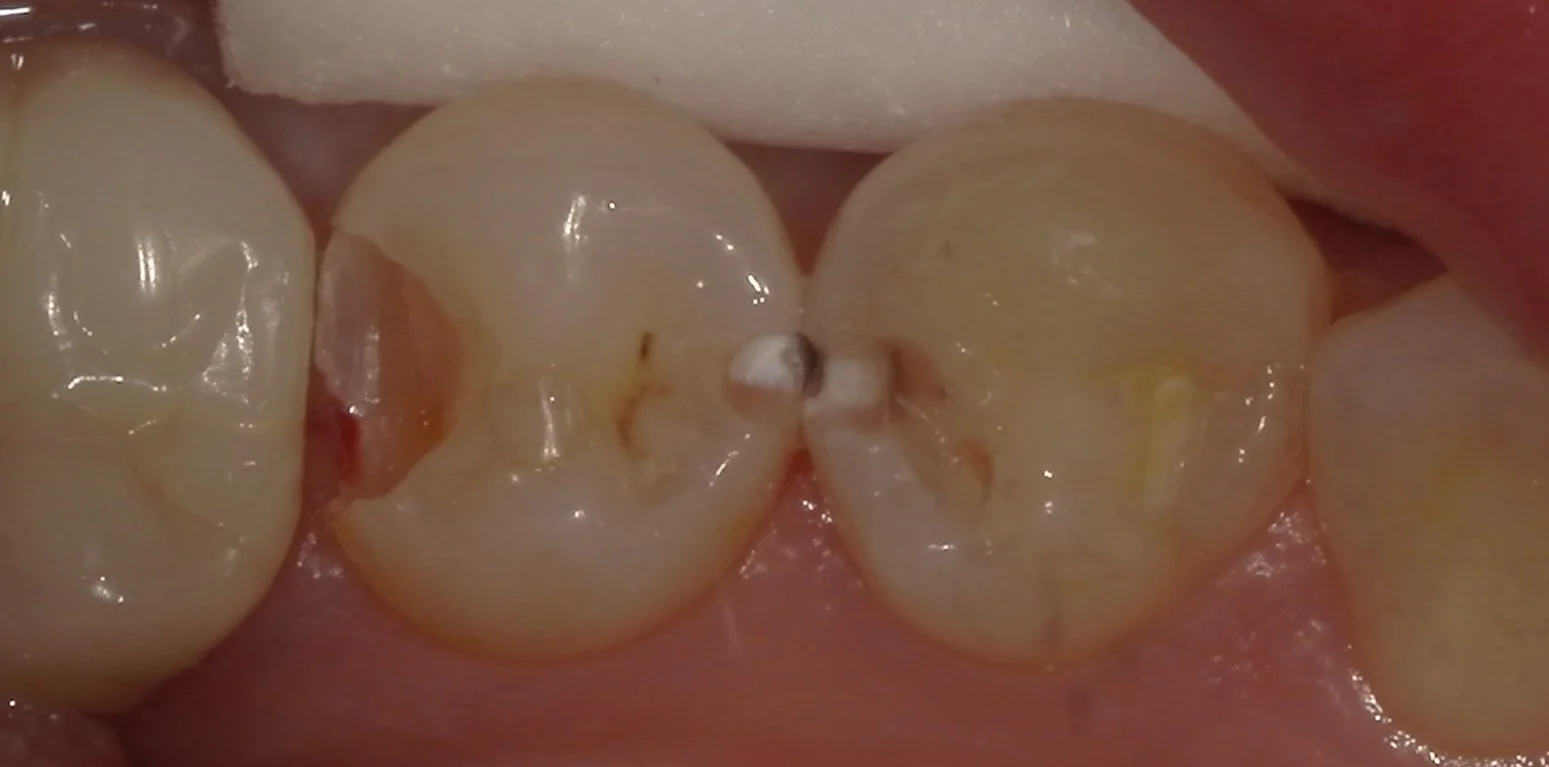

では術前の写真からです。

中央にある2本を治療したのですが、どこが虫歯か分かりますかね?

結構分かりづらいので、軽く削って分かりやすくしたのがこちらです。

歯の間の白い部分と黒い部分がある所が虫歯ですね。

あとは画面左側の茶色くなっているところ。これも虫歯です。